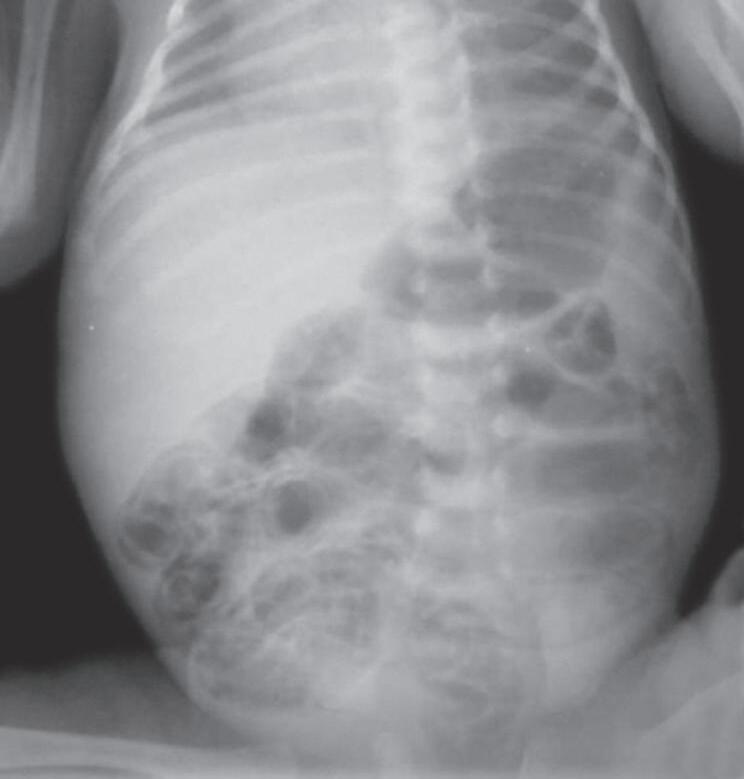

Aumento de bilirrubina direta e transaminases

Função renal pode ser acometida e alterações sugestivas de doenças oportunistas associadas

LCR: líquido cefalorraquidiano; VDRL: Estudo Laboratorial de Doenças Venéreas (do inglês Venereal Disease Research Laboratory); HIV: vírus de imunodeficiência humana.

Fonte: elaborada pelo autor.

ALTERAÇÕES DE